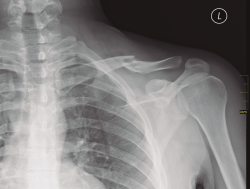

El examen radiológico debe consistir en radiologías simples de la clavícula y el hombro (Figura 2); también es recomendable una tomografía axial computarizada (TAC).

Figura 2. Radiografía simple de una fractura de clavícula en el tercio medio.